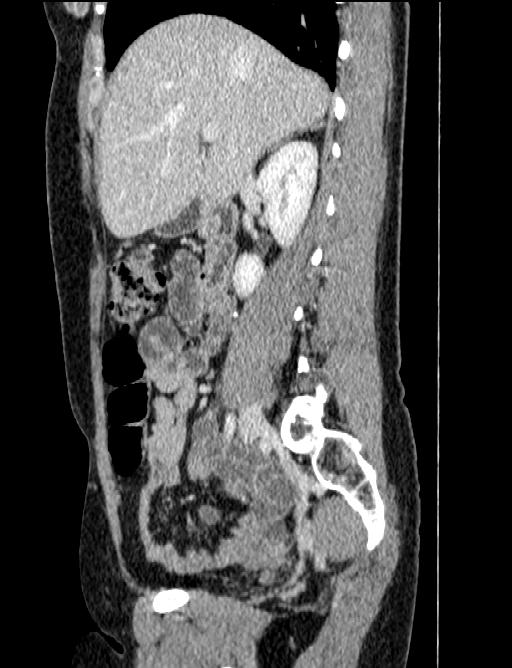

44 year old female with a long medical history. Undergone repeated surgeries for prox. 30 years. Not always fully understood what the purpose has been or expected outcome from all the procedures.

MRI August 2010.

Diagnose: There is no evidence to suspect that this patient may have an active phase of disease.